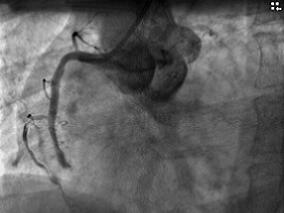

1小时条评论老年男性因急性下壁心肌梗死给予紧急介入治疗,即刻效果满意,临床症状消失,但术后半个月症状再发,如此危急情况怎样应对? 男性,63岁。 【主诉】 反复胸痛、胸闷4天。 【现病史】 2010年4月19日因急性下壁心肌梗死于外院行急诊PCI 治疗(图062‐1~图062‐3...